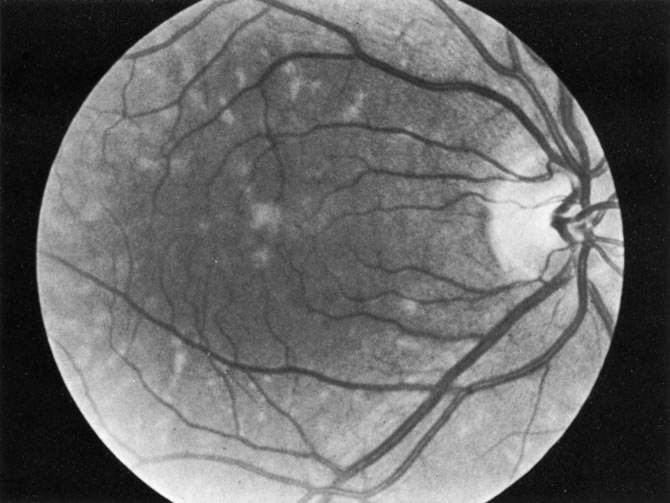

1. The intraocular findings in primary intraocular–CNS lymphoma may simulate a diffuse uveitis, usually with a plethora of vitreous cells and often with virtually pathognomonic yellowish white chorioretinal infiltrates (Fig. 20). Less common clinical presentations can mimic toxoplasmosis, acute retinal necrosis, a branch vein occlusion, or various forms of retinal vasculitis.

Fig. 20. Yellowish white chorioretinal infiltrate typical of primary intraocular lymphoma (erroneously termed ocular reticulum cell sarcoma). (Char DH: Clinical Ocular Oncology. 2nd ed. Philadelphia, Lippincott-Raven, 1996.)